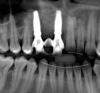

Fig 22. The implants selected for teeth Nos. 6 (Fig 22) and 8 (Fig 23) featured a tapered design.

Figure 22

Figure 23

Fig 24. At 3 months post immediate implant placement and provisionalization, complete regeneration of the defect and adequate osseous crest

levels and bone-to-implant contact were evident radiographically.

Figure 24

The bone graft underwent a 6-month maturation period to allow integration of the biomaterial. At this point, teeth Nos. 6 and 8 were atraumatically removed, and implants were immediately placed into the extraction sites without elevating a flap (Figure 19 through Figure 21). The gingival tissues exhibited a moderate degree of inflammation as a result of the difficult access for oral hygiene procedures under the post-orthodontic splint, which at the time had remained in place for 9 months. Implants featuring a tapered design were selected, and excellent primary stability was achieved (Figure 22 and Figure 23). Insertion torque values in excess of 45 Ncm were recorded for both implants, which allowed an immediate loading protocol.6,7,63,64

At the patient’s return visit 3 months after implant placement, the composite overlays were removed and the incisal edges of the provisional restoration were modified to approximate the length of the contralateral teeth. The patient reported no complaints, discomfort, or symptomatology throughout the osseointegration period. The implants were stable, and all discernable clinical parameters were within normal limits. The radiographic assessment revealed adequate bone-to-implant contact and osseous crest levels. Similarly, the peri-implant soft tissues displayed a healthy appearance and satisfactory gingival margin architecture (Figure 24 through Figure 27).